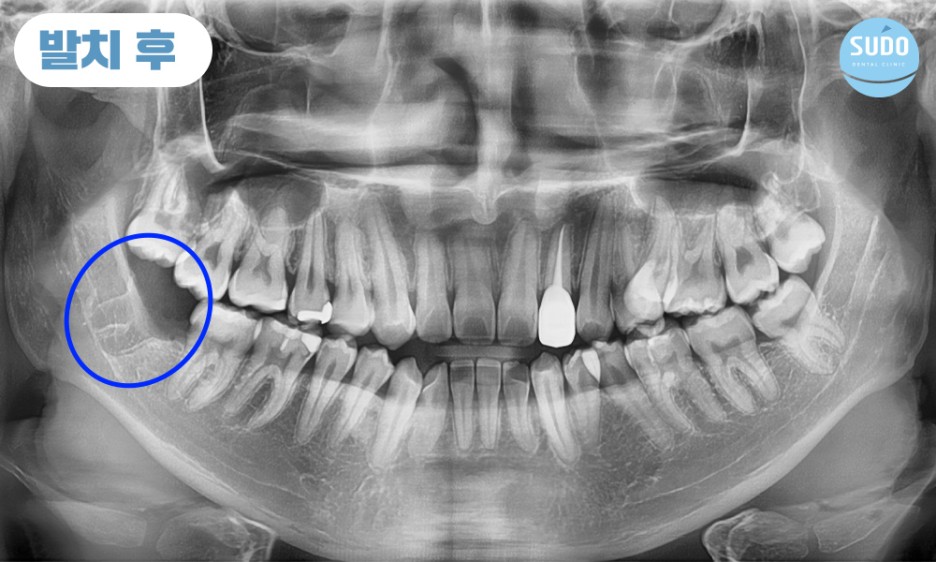

본 환자분은 20대 초반의 남성분으로 오른쪽 아래 매복되어 있는 사랑니에 충치가 심하게 진행되어 치아 일부가 이미 파절된 상태로 본원에 내원해 주셨습니다.

X-ray를 촬영해 보니 치아 뿌리 끝이 신경관과 매우 근접한 상태였습니다. 신경관 손상 가능성이 있어 까다로운 케이스였는데, CT로 촬영하여 정밀 분석한 결과를 토대로 환자분의 충분한 상담을 통해 발치를 진행하기로 했습니다.

4개 모두 사랑니가 맹출했지만 발치는 처음인 본 환자분의 두려움을 덜어드리기 위해 발치 과정을 꼼꼼하고 자세히 설명드렸기에 환자분께서도 큰 불편함 없이 발치할 수 있었다고 말씀해 주셨습니다.

파노라마 사진에서 보이는 것과 같이 아래쪽 어금니 아래는 많은 신경들이 지나갑니다.

발치를 하다가 신경을 잘못 건드릴 위험이 있기 때문에 정밀한 진단이 가능한 3차원 영상 장비를 갖추고 있는지, 풍부한 임상경험과 노하우를 겸비한 의료진이 상주하고 있는지 확인하는 것이 중요합니다.